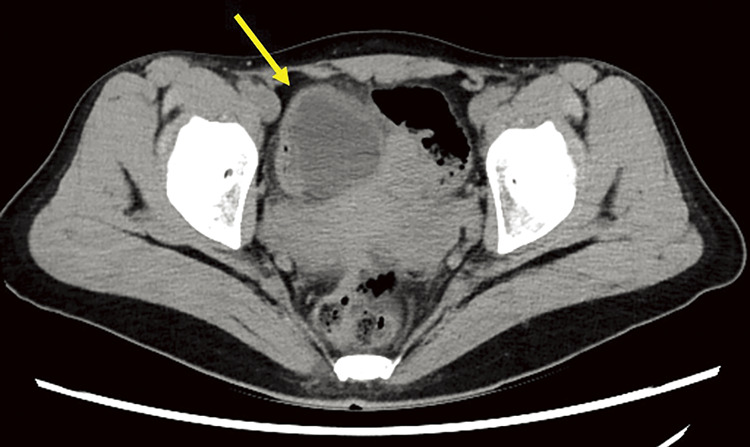

Case presentation: A woman in her thirties visited the emergency department with persistent lower abdominal pain. Physical examination and laboratory tests, including those for tumor markers, were unremarkable. CT revealed a cystic mass near the uterus, and pelvic MRI revealed a cystic lesion that had migrated during follow-up imaging. Cine MRI showed peristaltic movements within the lesion, and abdominal ultrasonography confirmed a cystic structure with wall movements resembling intestinal peristalsis. Based on these findings, the diagnosis of a noncommunicating small bowel duplication cyst was made.The patient underwent a laparoscopic single-port partial resection of the ileum. A cystic lesion located 75 cm proximal to the terminal ileum was excised along with a segment of the small intestine. Histopathological examination revealed a duplicated cyst lined with the small intestinal mucosa, confirming the diagnosis. The postoperative course was uneventful, and the patient was discharged 1 week postoperatively.